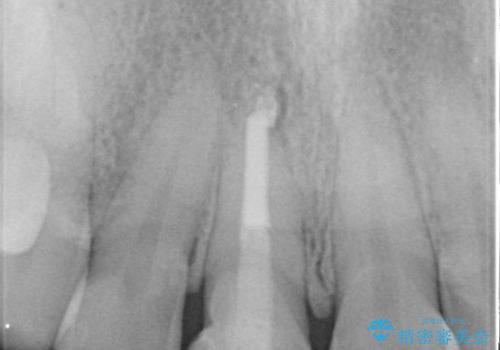

- 前歯のガタつき、変色を主訴に来院された患者様です。術前診査のCT撮影にて、変色した前歯の根の先に病巣があることが判明しました。そこで、マウスピースによる矯正治療と、前歯の根管治療、かぶせ物のやり直し治療を並行して行いました。